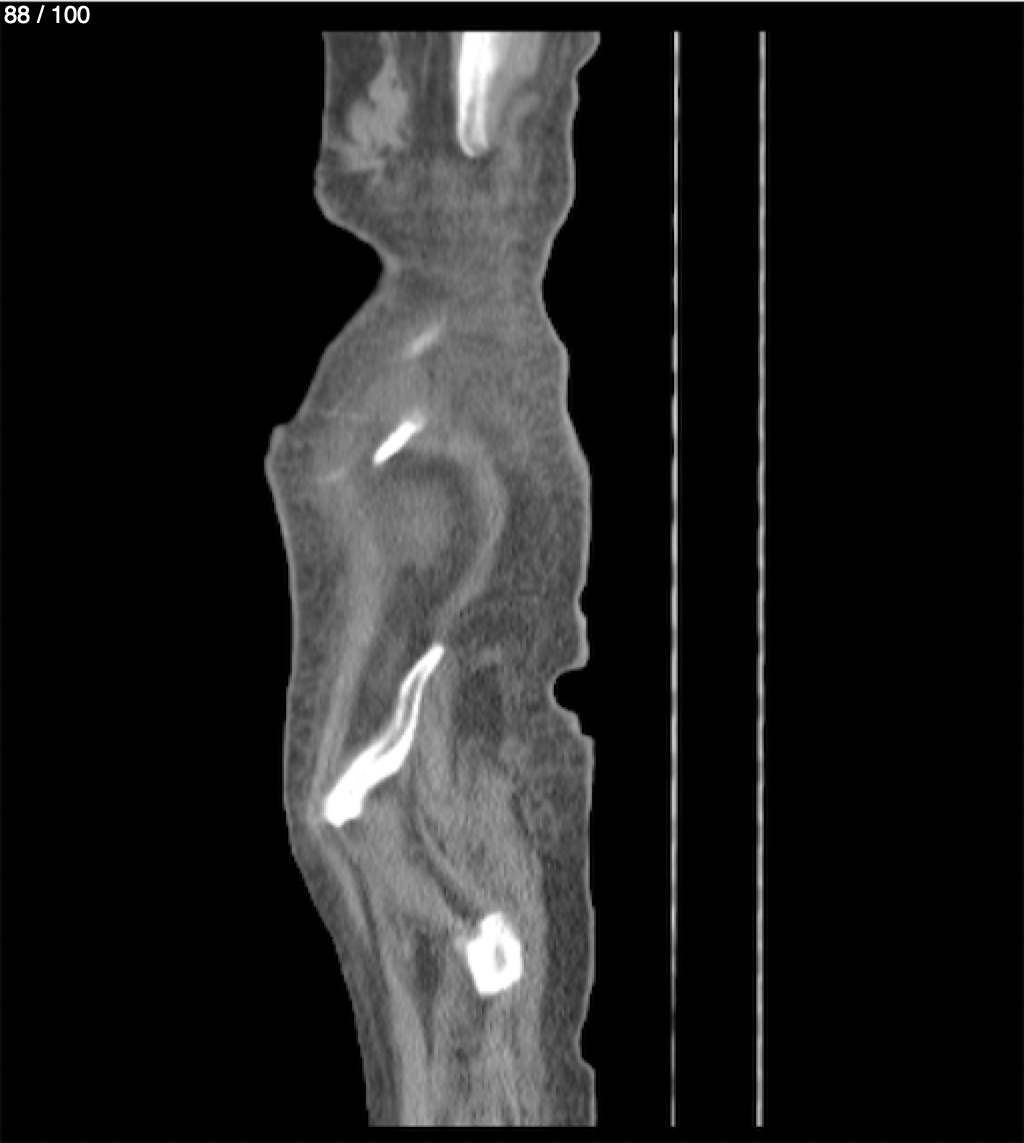

Hilda Geronimo Mendez 60A - T.C Abdomen Simple